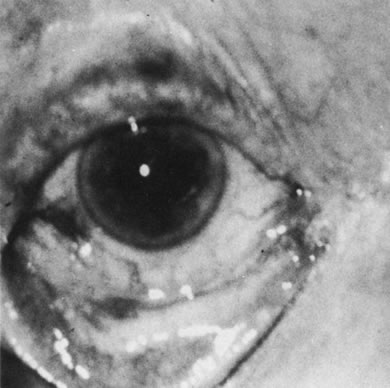

Necrotic melanomas account for approximately 5% of uveal melanomas; in the majority of cases, there is intraocular inflammation accompanying the cataract.7–9Figures 1 and 2 demonstrate a typical case. The patient had a long history of unilateral decreased vision. The eye had become painful 1 month before admission, and he was referred for evaluation of uveitis. Clinically, there was a dense, unilateral cataract with significant intraocular inflammation, which was manifested as a ciliary flush with 2+ cells and flare. Media opacity obscured all fundus detail. An immersion B-scan demonstrated a large intraocular tumor that was most consistent with a uveal melanoma. The eye was removed, and the diagnosis was confirmed histologically.10

|